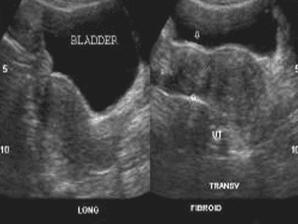

U xơ cơ tử cung thành trước tử cung

U xơ cơ tử cung thành sau tử cung dưới thanh mạc, tăng âm do thành phần xơ nhiều hơn cơ